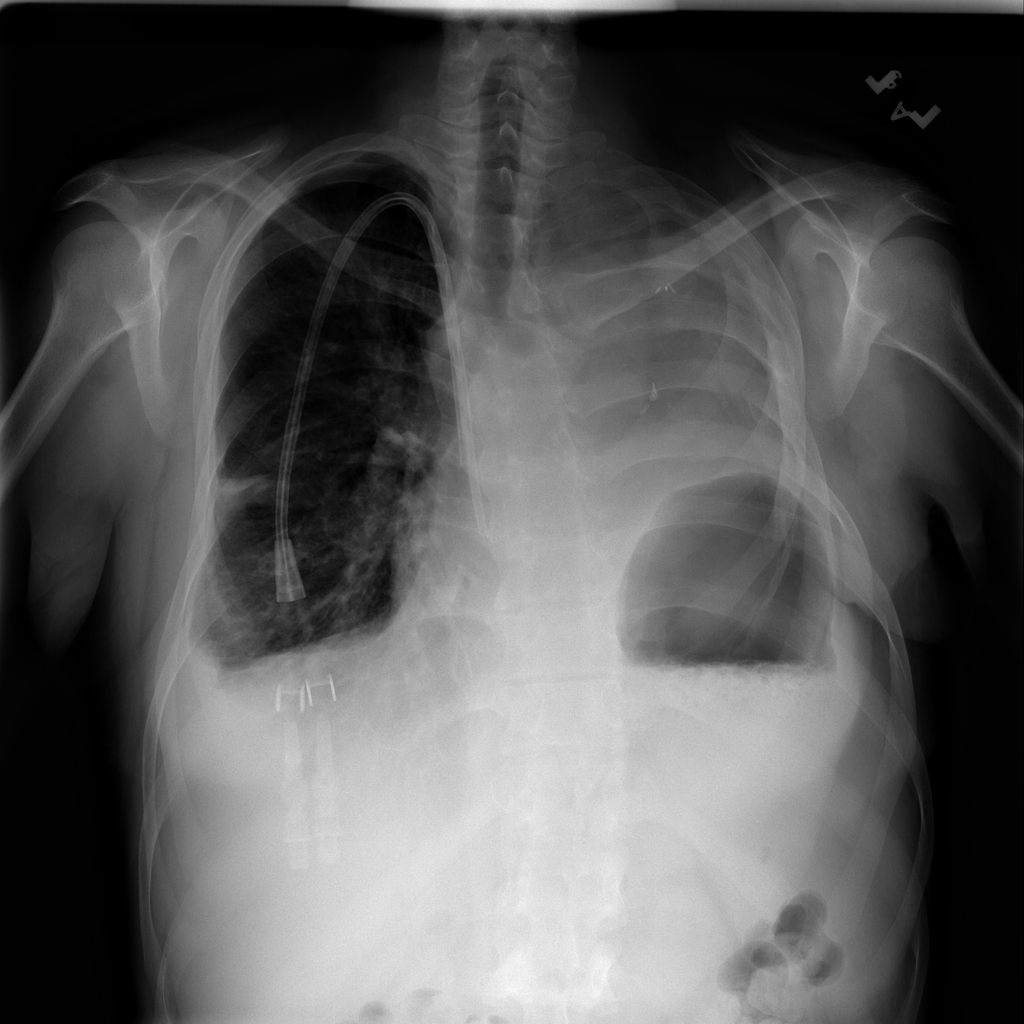

PAT-40F9 · IMG-004Effusion

PAT-40F9 · IMG-004

PA